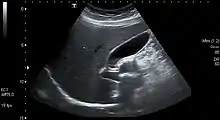

Gallstones form when the bile is saturated, usually with either cholesterol or bilirubin.[18] Most gallstones do not cause symptoms, with stones either remaining in the gallbladder or passed along the biliary system.[19] When symptoms occur, severe "colicky" pain in the upper right part of the abdomen is often felt.[18] If the stone blocks the gallbladder, inflammation known as cholecystitis may result. If the stone lodges in the biliary system, jaundice may occur; if the stone blocks the pancreatic duct, pancreatitis may occur.[19] Gallstones are diagnosed using ultrasound.[18] When a symptomatic gallstone occurs, it is often managed by waiting for it to be passed naturally.[19] Given the likelihood of recurrent gallstones, surgery to remove the gallbladder is often considered.[19] Some medication, such as ursodeoxycholic acid, may be used; lithotripsy, a procedure used to break down the stones, may also be used.[19]

An ultrasound is often the first medical imaging test performed when gallbladder disease such as gallstones are suspected.[19] An abdominal X-ray or CT scan is another form of imaging that may be used to examine the gallbladder and surrounding organs.[19] Other imaging options include MRCP (magnetic resonance cholangiopancreatography), ERCP and percutaneous or intraoperative cholangiography.[19] A cholescintigraphy scan is a nuclear imaging procedure used to assess the condition of the gallbladder.[26]